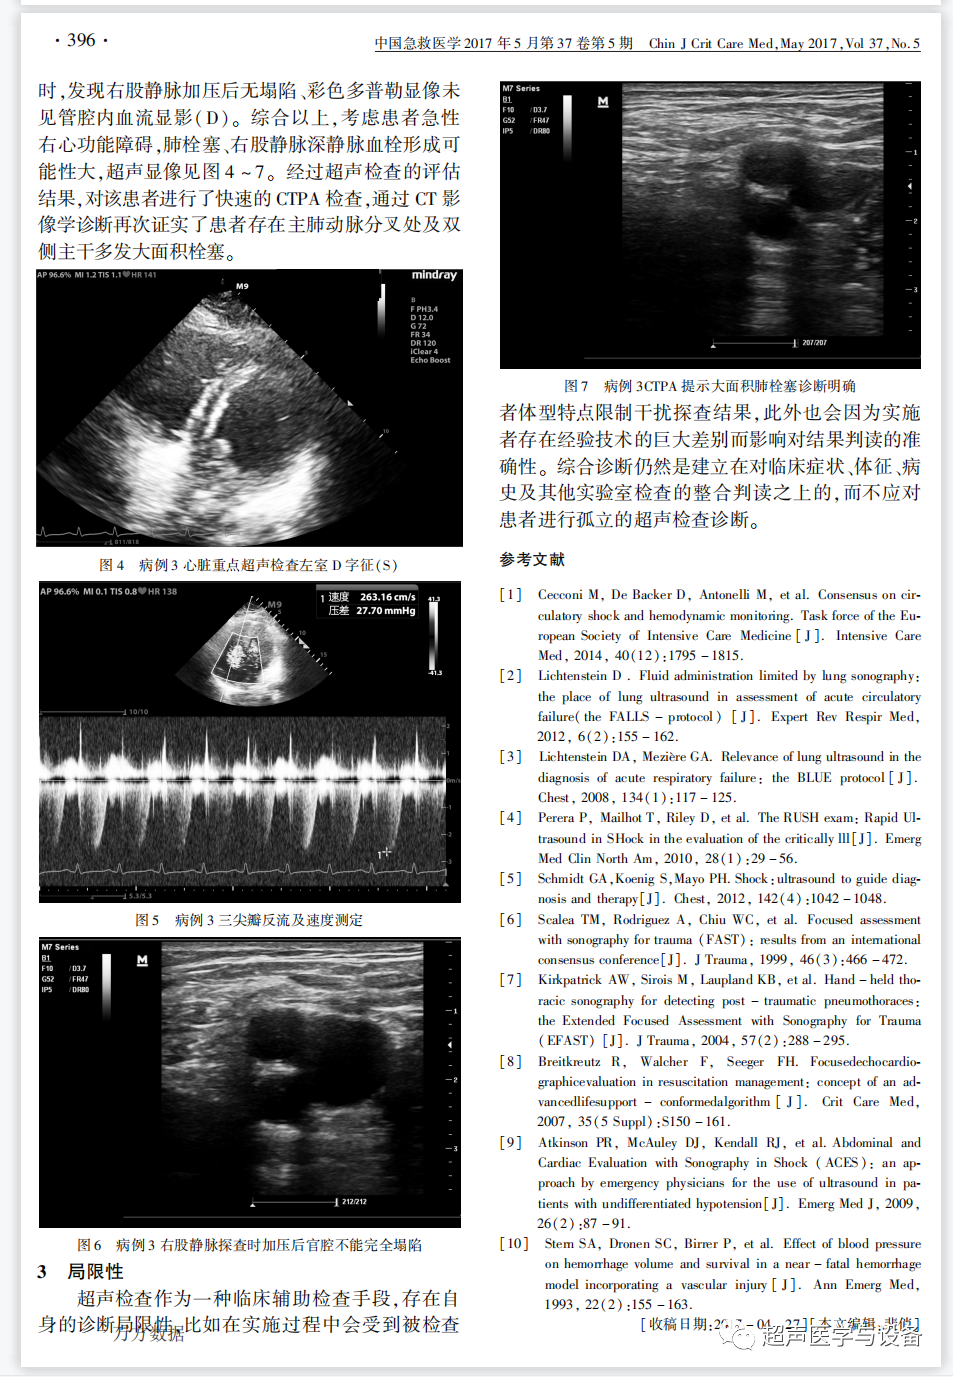

以案说理,3个病例,不明原因休克鉴别诊断,急诊超声大显身手,成都林远恒医生